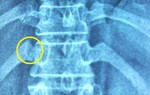

Theo Tổ chức Nghiên cứu Ung thư Vương Quốc Anh, nếu khối u ác tính xuất hiện ở đỉnh phổi gọi là hội chứng Pancoast. Hội chứng này thường biểu hiện bằng các cơn đau vai trầm trọng. Cơn đau có thể lan xuống cánh tay hoặc lên đầu và cổ.

Nguyên nhân là do khi khối u phát triển ở đỉnh phổi sẽ ảnh hưởng tới dây thần kinh cánh tay và gây đau ở vai, cánh tay.